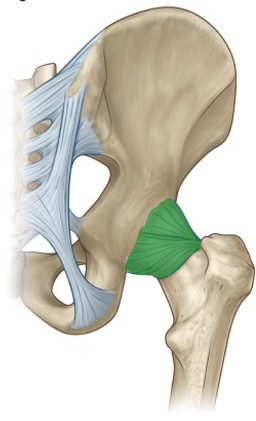

What is this structure?

Ischiofemoral ligament of hip

What is this structure?

Ileofemoral ligament of hip

What is this structure?

Pubofemoral ligament of hip